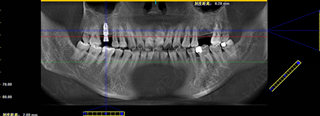

种牙完成后口腔ct全景片